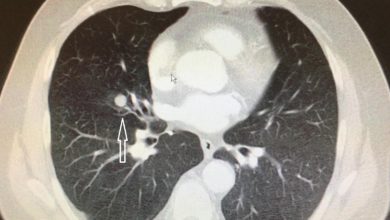

Bir bu tabir eksikti – akciğerde nodül

Hepimiz kanser veya selim tümör kavramlarını iyi biliyoruz. Fakat son yıllarda radyoloji raporlarını dikkatli inceleyen kişiler, akciğerde 3 mm, 5…